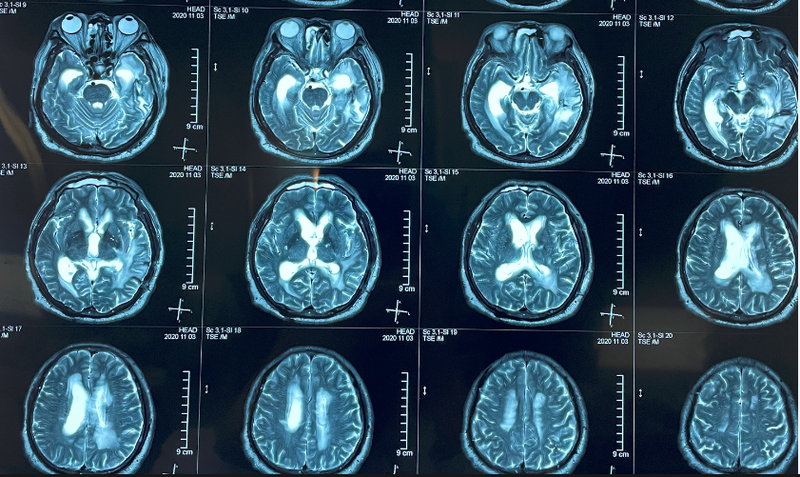

患者,男,56歲,2020-7發(fā)病,2021-2-18入院。【病史】患者2020-7因中耳炎未及時(shí)治療,出現(xiàn)左耳流膿、劇烈頭痛、逐漸意識(shí)模糊、高熱躁動(dòng),頭CT示腦膿腫可能,行腰椎穿刺,診斷“腦室炎,左顳腦膿腫”,行“雙額鉆孔側(cè)腦室穿刺置管引流術(shù)”“腦膿腫穿刺引流術(shù)”。頭顱核磁示:左側(cè)顳葉腦膿腫,周?chē)竺娣e水腫,輕度腦疝。經(jīng)治療后患者意識(shí)轉(zhuǎn)清,肢體活動(dòng)自如,基本生活自理,唯遺留語(yǔ)言障礙,以聽(tīng)理解障礙為主。為求語(yǔ)言康復(fù)來(lái)我科住院治療。?其言語(yǔ)表現(xiàn)特征:1.聽(tīng)不懂,答非所問(wèn),無(wú)法交流。(問(wèn):您身高多少?答:我沒(méi)帶手表)2.找詞困難,不能命名(指著電燈問(wèn)患者:這是什么??患者回答不出,或亂答如“蘋(píng)果”,或自編新奇詞匯,狀態(tài)好時(shí)可描述為“黑天用的”)3.語(yǔ)言流利、語(yǔ)量多、但缺乏實(shí)詞、有新奇詞匯(說(shuō)話滔滔不絕,但因語(yǔ)句缺乏實(shí)詞而未表達(dá)出語(yǔ)義)4.復(fù)述正常5.反應(yīng)慢,記憶力差,間斷性不認(rèn)識(shí)女兒(當(dāng)作妹妹)?;颊唢D葉損傷,或伴隨認(rèn)知障礙,但在失語(yǔ)下暫無(wú)法評(píng)價(jià)其認(rèn)知能力。?【影像學(xué)檢查】核磁:病灶位于左顳葉內(nèi)側(cè),累及顳前部、顳中回后部,膿腫炎性刺激局部血管痙攣造成繼發(fā)性缺血改變,缺血累及左顳葉皮層下白質(zhì)、左側(cè)海馬、側(cè)腦室后角周?chē)踪|(zhì)等區(qū)域,并可見(jiàn)明顯顳葉腦區(qū)皮層變薄。?【評(píng)估】入院后行漢語(yǔ)失語(yǔ)證心理語(yǔ)言評(píng)估(PACA)測(cè)評(píng):聽(tīng)詞指圖9/30看詞指圖8/30真詞非詞聽(tīng)判斷17/30(是、否二選一回答)圖命名0/5?(回答為無(wú)關(guān)詞匯,部分詞匯可描述,電燈-“黑天用的”,輪船-“裝東西用的”,葡萄-“提著”)復(fù)述?15/15朗讀?5/10印象:聽(tīng)理解差、閱讀理解差、不能命名,朗讀、書(shū)寫(xiě)部分保留,復(fù)述良好。診斷:經(jīng)皮質(zhì)感覺(jué)性失語(yǔ)。其語(yǔ)言主要的損傷環(huán)節(jié):詞匯通達(dá)、詞匯提取。?【治療方案】1.經(jīng)顱直流電刺激?治療部位以顳上回后部(wernick區(qū),聽(tīng)理解)、顳中回后部(改善詞匯提?。⑶帮D(語(yǔ)義系統(tǒng))、DLPFC(改善認(rèn)知)、顳頂交界區(qū)(聽(tīng)覺(jué)表征到言語(yǔ)運(yùn)動(dòng)的轉(zhuǎn)換)為主。療程:1天2次,各20min,每周5天。2.言語(yǔ)行為治療:以改善聽(tīng)理解為主,通過(guò)復(fù)述訓(xùn)練命名,佐以閱讀、書(shū)寫(xiě)訓(xùn)練。?【治療效果】該患者失語(yǔ)程度較重,第一療程3周后聽(tīng)理解、閱讀理解明顯提高,聽(tīng)詞指圖、看詞指圖成績(jī)提高50%,效果滿意。之后進(jìn)步速度減慢,出現(xiàn)平臺(tái)期,但在治療3個(gè)月后整體成績(jī)均有明顯改善。后患者返回外地,停止治療,因經(jīng)顱直流電刺激在停止治療后仍可有持續(xù)的后效應(yīng),教給家屬方法在家自行言語(yǔ)訓(xùn)練,半年后復(fù)診,成績(jī)較前仍有少量進(jìn)步。最終,患者聽(tīng)理解成績(jī)由9分提高到20分,看詞指圖成績(jī)由8分提高到14分,命名由0分提高到12分。語(yǔ)言表現(xiàn):與患者可簡(jiǎn)單交流,基本可滿足家庭日常交流需求,輔助下可完成簡(jiǎn)單的社交(聊天、問(wèn)路、購(gòu)買(mǎi)東西等)。